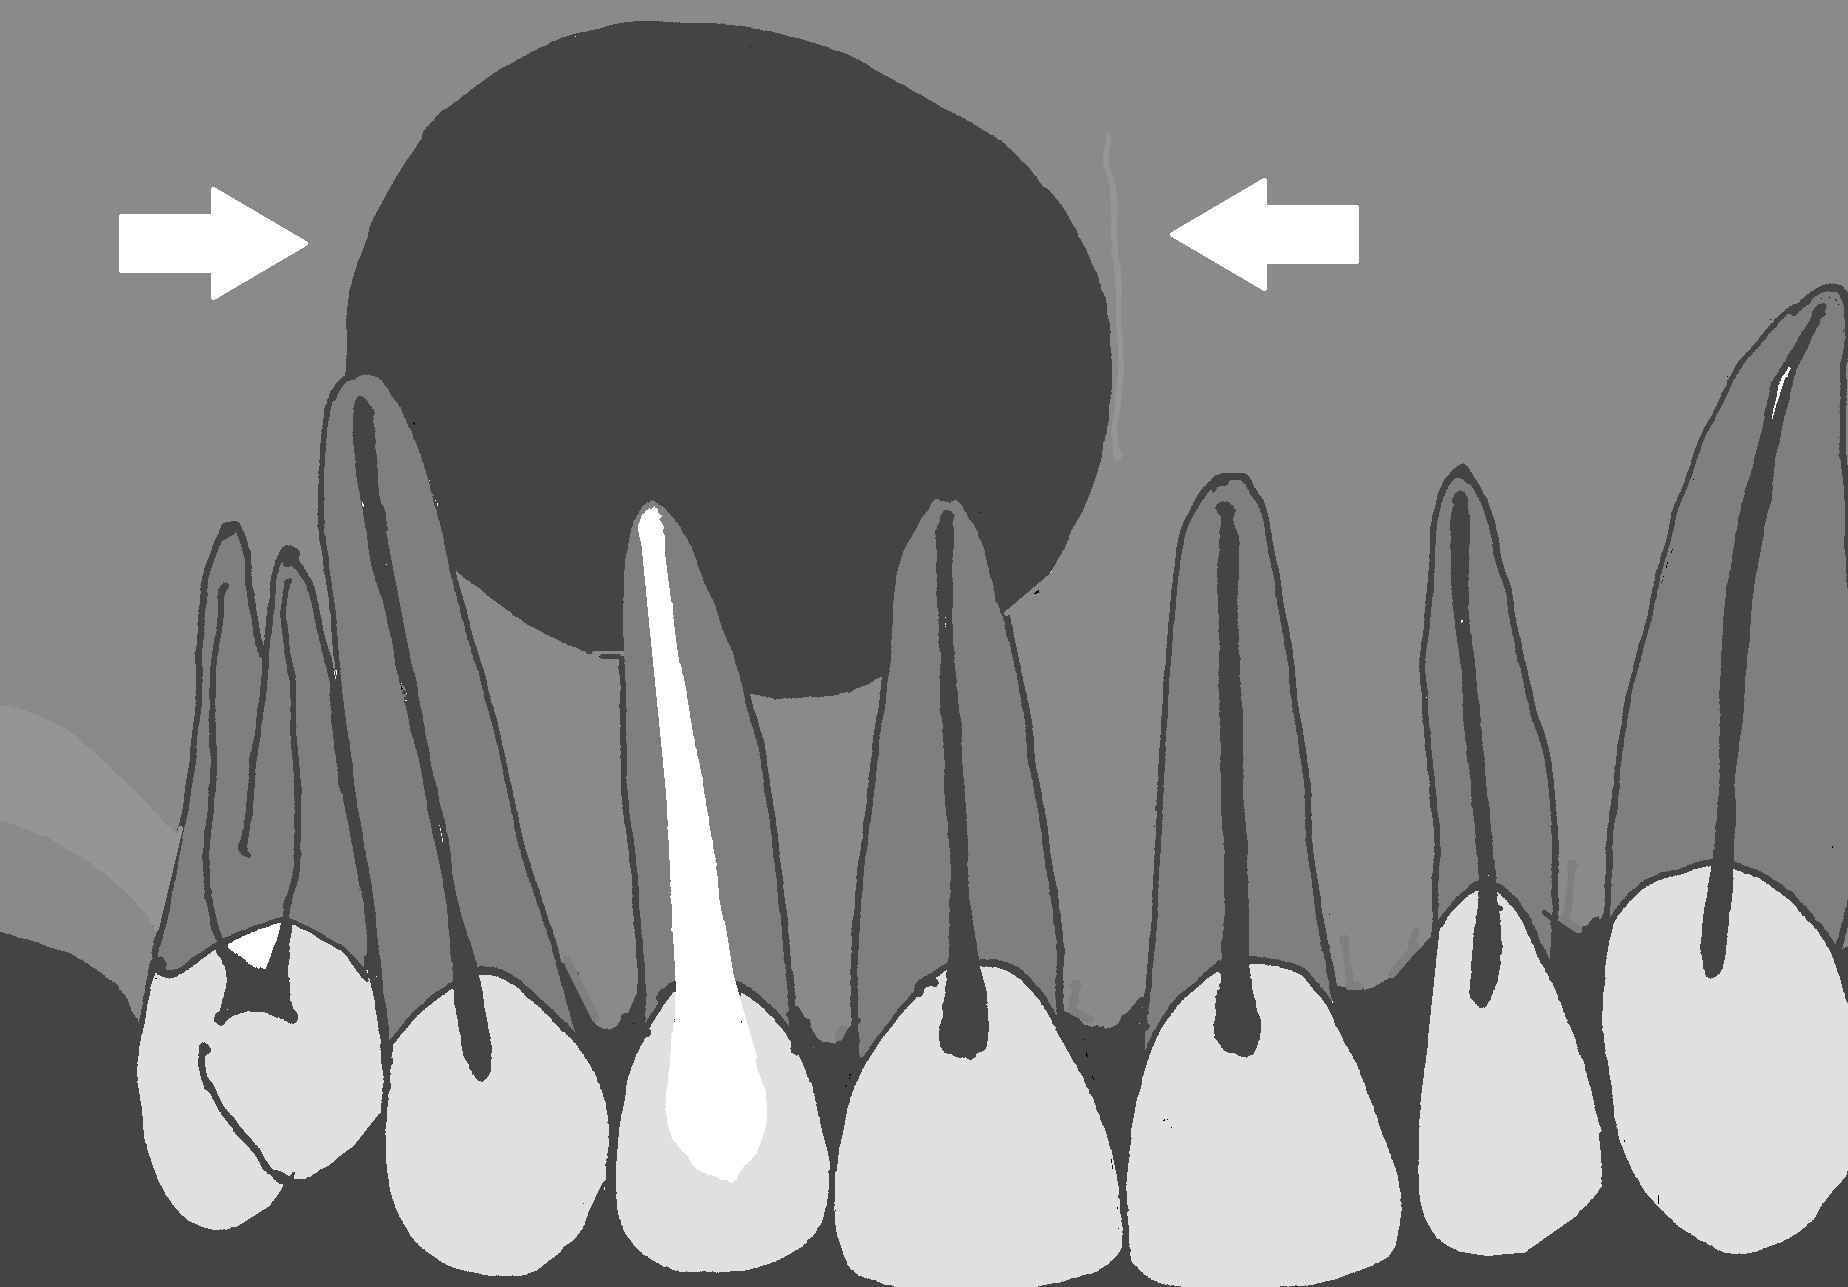

Pacjentka, lat 41, została skierowana do Zakładu Endodoncji Uniwersytetu w Mansoura (Egipt) na konsultację i ewentualne leczenie endodontyczne zęba siecznego bocznego prawego szczęki. Zapalną zmianę okołowierzchołkową wykryto przypadkowo podczas rutynowego badania radiologicznego. Pacjentka nie zgłaszała jakichkolwiek dolegliwości. Skarżyła się wyłącznie na trudności w żuciu pokarmu, co związane było z utratą wielu zębów bocznych. Badanie kliniczne wykazało znaczne zniszczenie próchnicą korony zęba siecznego bocznego prawego szczęki. Badanie palpacyjne nie wykazało bolesności wyrostka okolicy wierzchołka korzenia. Na zaleconym pantomogramie stwierdzono rozległą zmianę zapalną obejmującą również korzenie zębów 11 i 13 (ryc. 1). W badaniu klinicznym nie stwierdzono bolesności ww. zębów podczas opukiwania; również wyrostek na wysokości wierzchołków korzeni nie był bolesny podczas badania palpacyjnego. Natomiast badanie wrażliwości miazgi prądem faradycznym oraz na zimno dało negatywny wynik (brak jakichkolwiek reakcji). Stan przyzębia brzeżnego zębów nie budził zastrzeżeń. Na podstawie badania klinicznego i badań dodatkowych rozpoznano torbiel korzeniową zęba 12. Po rozmowie z pacjentką podjęto decyzję o wyłuszczeniu torbieli. Pacjentka została umówiona na leczenie kanałowe zęba przyczynowego oraz zębów sąsiednich.

Ryc. 1. Schemat obrazujący opisywaną sytuację kliniczną. Rozległa torbiel (strzałki), poza korzeniem zęba 12, obejmuje także wierzchołki korzeni zębów 11 i 13.